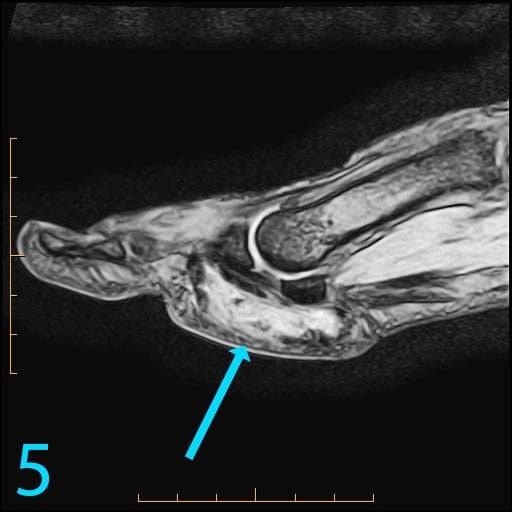

This 18-year-old female presents with a palpable soft tissue mass subjacent to the first metatarsophalangeal (MP) joint that she has noticed for 1-2 months. It is painful with shoes and ambulation, and you are evaluating her for a soft tissue tumor. What is the cause of her problem, and what pertinent negatives must you notice?

This patient has a so-called "pressure lesion" due to ambulation, with associated adventitial bursa/pseudobursa formation within. It is a chronic process. This is manifested as a large, ovoid mass-like structure within the subcutaneous soft tissues along the plantar aspect of the first MP joint and sesamoid bones (arrow). It is well-circumscribed and demonstrates a mildly lobulated configuration. There is peripheral signal hypointensity indicating a rim or rind of fibrosis, and there is intermediate to high T2 signal centrally, suggesting a component of complex fluid. The major differential diagnosis is fibroma of tendon sheath. This is a counterintuitive diagnosis as fibrous lesions are typically dark on all pulsing sequences. But, fluid signal from the tendon sheath may be found in this specific fibrous tumor. So, fibromas of tendon sheath are typically hyperintense centrally.

While the lobulation of the lesion medially is reminiscent of plantar fibromatosis, the constellation of findings remains most compatible with a giant pressure lesion. Fibromatosis (non-aggressive type) occurs more proximally in the middle aponeurotic cord of the plantar fascia. The findings are not suspicious of an aggressive neoplastic lesion (based on location and concentric shape), and you can also rule out MP joint capsulitis and Morton's neuroma because of location. You should always rule out plantar plate tear along the second MP joint on thin section sagittals if you have a large pressure lesion under the second metatarsal head. For more case review, visit MRI Online.